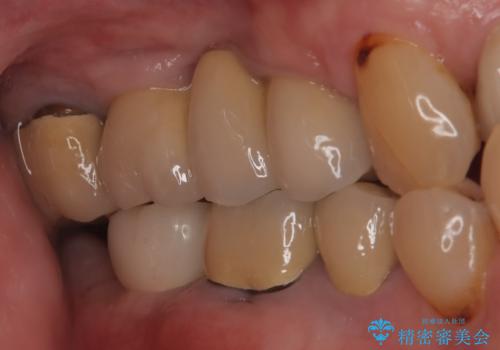

【インプラント】 他院で入れた被せ物が取れた

- 「他院で治療した被せ物が外れた」を主訴に来院された患者様です。診査診断を行い歯の保存が困難だったため抜歯後、インプラントで治療しました。

インプラントを入れるためには十分な骨の高さと幅が必要です。術前に検査を行い必要であれば別途、骨や角化歯肉を増やす治療も行う事があります。

インプラントの土台と被せ物は適合が良い物を制作するため、シリコン印象材を使用し型を取っています。